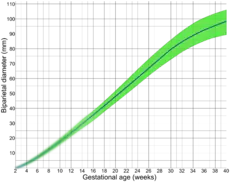

Following are diagrams for estimating gestational age from obstetric ultrasound, by various target parameters:

By crown-rump length (CRL) By biparietal diameter (BPD)

The mean pregnancy length has been estimated to be 283.4 days of gestational age as timed from the first day of the last menstrual period and 280.6 days when retrospectively estimated by obstetric ultrasound measurement of the fetal biparietal diameter (BPD) in the second trimester.[10] Other algorithms take into account other variables, such as whether this is the first or subsequent child, the mother's race, age, length of menstrual cycle, and menstrual regularity. In order to have a standard reference point, the normal pregnancy duration is assumed by medical professionals to be 280 days (or 40 weeks) of gestational age. Furthermore, actual childbirth has only a certain probability of occurring within the limits of the estimated due date. A study of singleton live births came to the result that childbirth has a standard deviation of 14 days when gestational age is estimated by first-trimester ultrasound and 16 days when estimated directly by last menstrual period.[9]